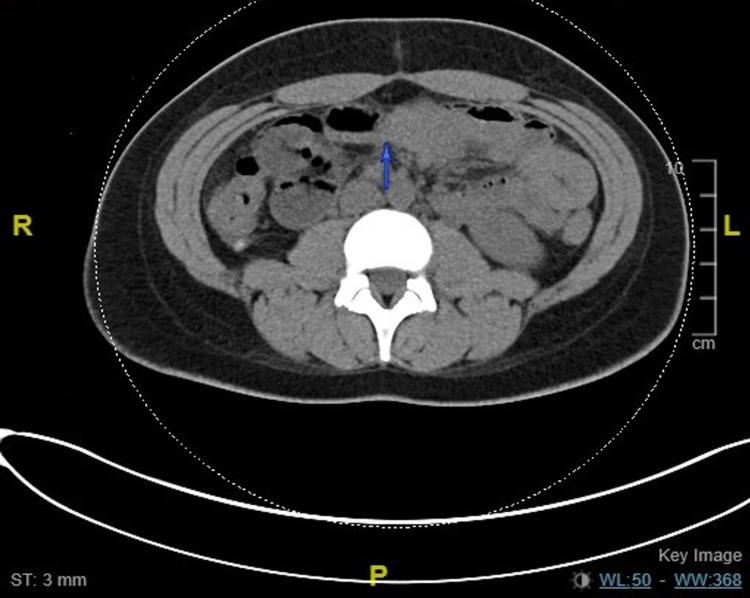

黑斑息肉综合征所致肠套叠

Intussusception Caused by Peutz-Jeghers Syndrome.

A 20-year-old female patient with a family history significant for Peutz-Jeghers syndrome presented to the hospital multiple times with complaints of abdominal pain. On the initial visit to the hospital, the patient underwent small bowel resection for small bowel obstruction secondary to intussusception, following which she visited the hospital again one year later for similar complaints and underwent reduction of multiple points of intussusception of the small bowel without any resection of the same. Eventually, the patient underwent resection of the small bowel for the second time, along with tumor resections. The importance of follow-up in patients with Peutz-Jeghers is particularly essential, in part, because it is vital to monitor the tumors, their size, and number to prevent surgical intestinal complications, anemia, and also to eventually monitor for carcinomatous changes.

摘要